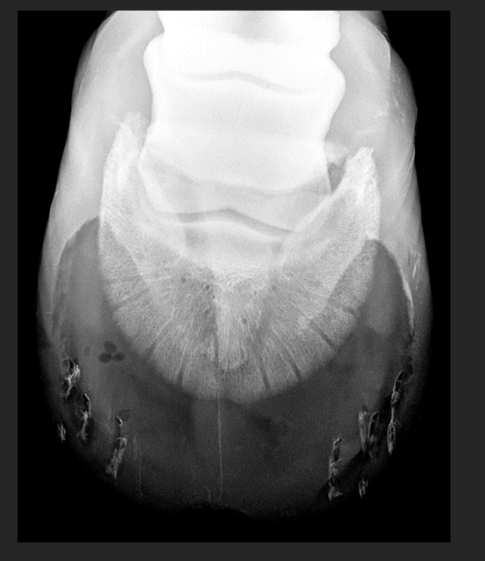

in hoof abscesses, the abscess itself cannot be seen but gas produced by bacteria can be seen such as in this image (3 dark bubbles)

the radiating tracks or lines are from removed shoe nails.